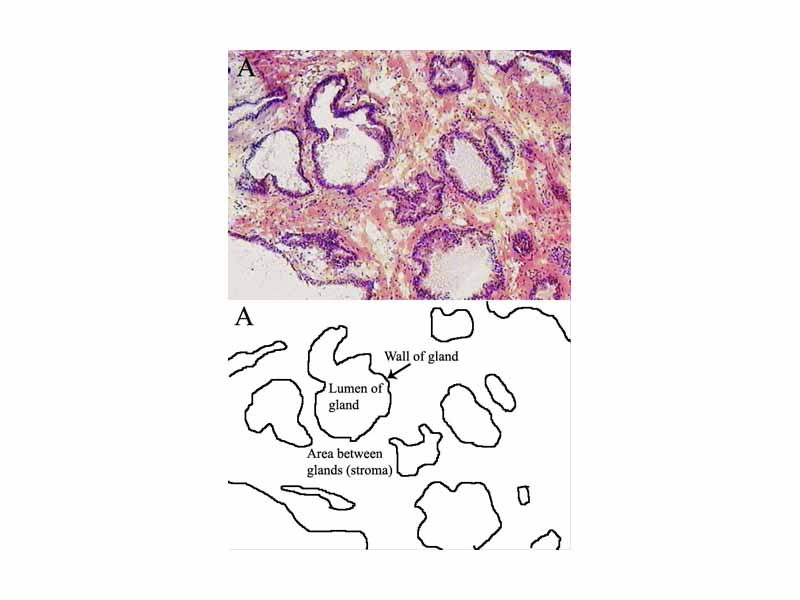

Prostate histology